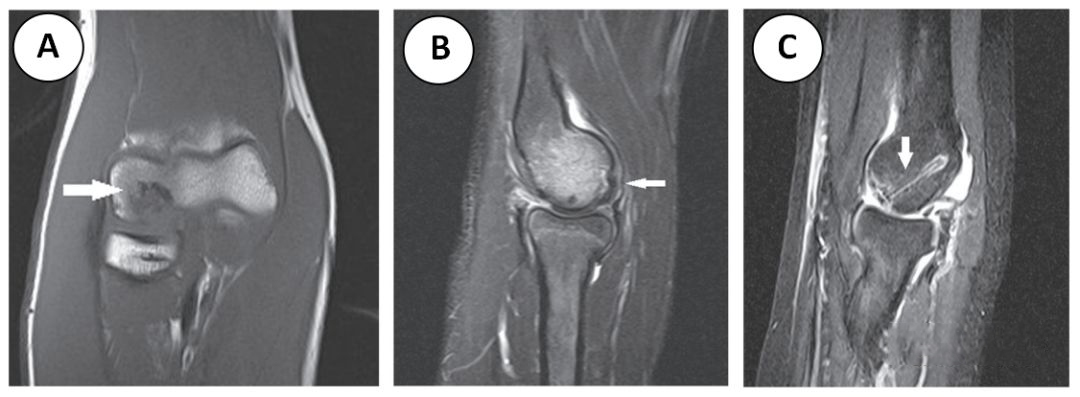

图四 (A) 冠状位 T1 和 (B) 矢状位 STIR 图像显示肱骨小头前正中部信号异常的病灶区 (箭头所示),但没有高的流体信号,所以病灶是稳定的。STIR 图像显示肱骨小头前方水肿。一名 13 岁的剥脱性肱骨小头骨软骨炎患者接受了螺钉固定。(C) 矢状位 STIR 图像显示完整的螺钉 (箭头),病灶区碎片稳定,位置满意。

图四